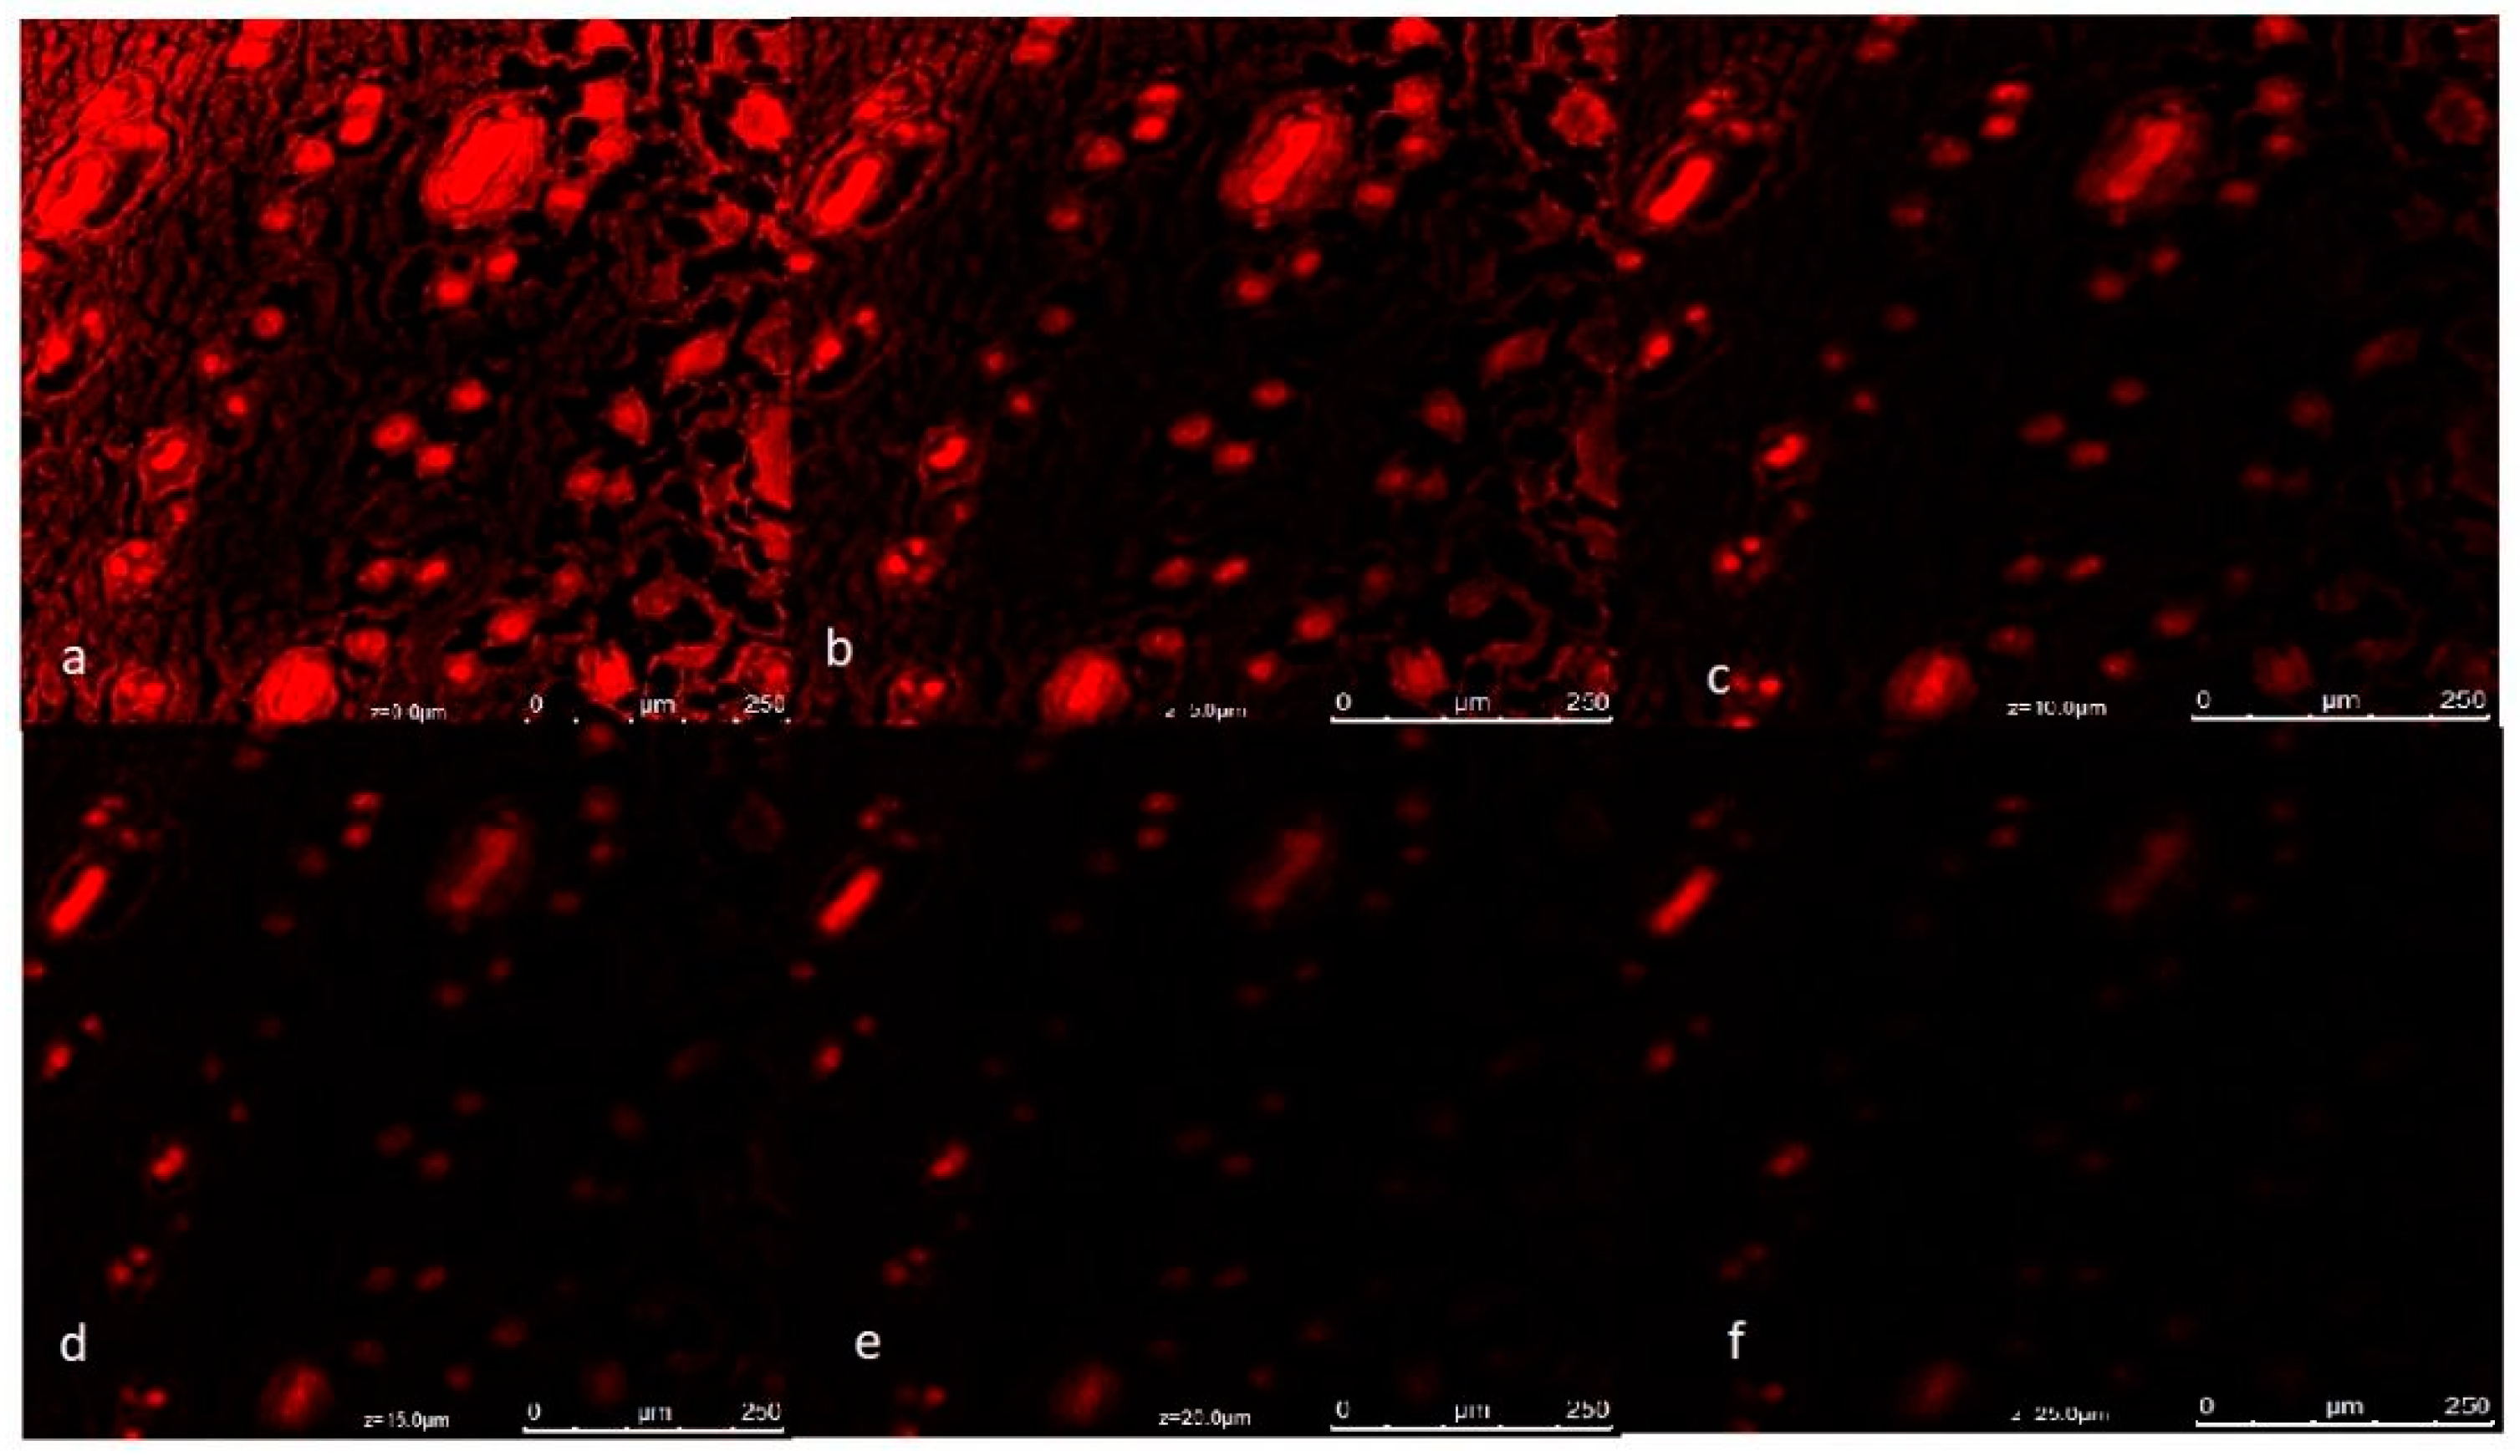

3.10. Confocal Laser Scanning Microscopy